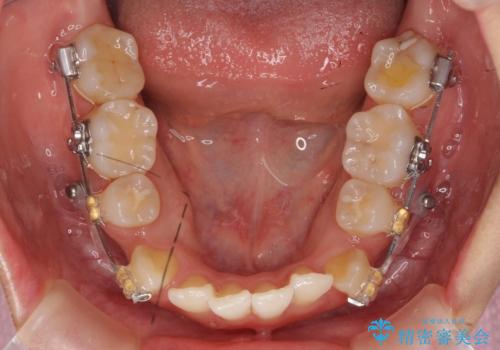

- 20代女性

- 矯正装置

- 審美装置

- 治療期間

- 2年3ヶ月

- 治療計画

- 前歯のがたつきと正中のずれを主訴に来院。

小臼歯を4本抜歯しています。